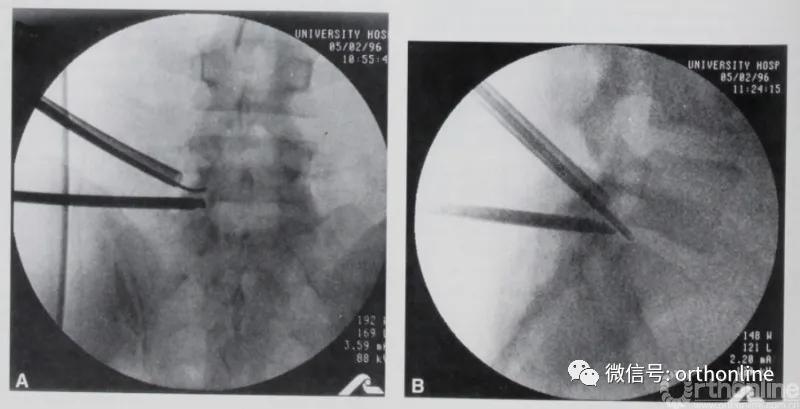

图4

图4. 1997年Osman使用的单侧双通道脊柱内镜技术。引自Osman SG, Marsolais EB. Endoscopic transiliac approach to L5-S1 disc and foramen. A cadaver study. Spine (Phila Pa 1976) 1997;22(11):1259-1263.